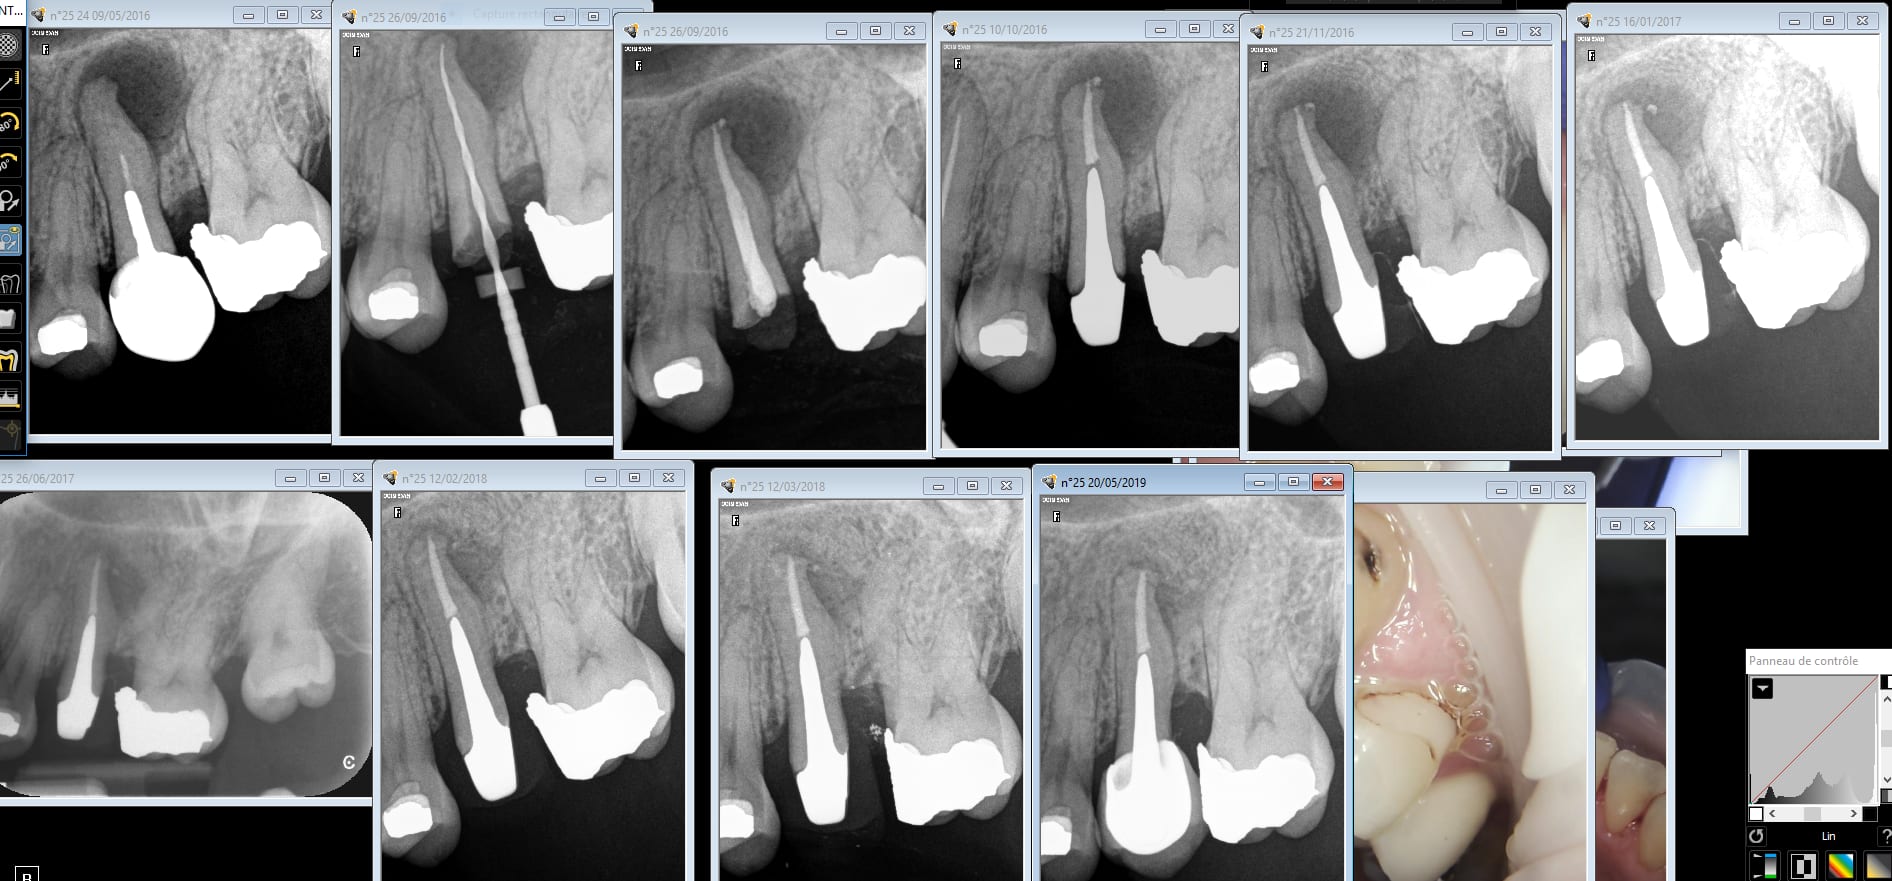

Ic clavette rte 1 2019 02 05 11.53 - Eugenol

Rte 25 bznxbw - Eugenol